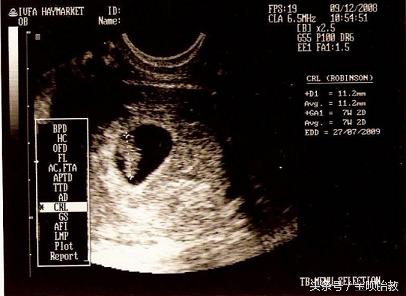

言归正传,看B超的胎囊就可以猜男女,那么胎囊到底是什么呢?

什么是胎囊?

胎囊,也叫孕囊,是怀孕最初胚胎的形态。

如何正确的胎囊看男女?

2、看形状:

像茄子或长条状的是男宝宝可能性大,圆圆的是女宝宝可能性大。

孕囊都是圆柱状的,每个B超师做B超的时候,截面会截取的方位不一样,有的横截面,有的截取竖截面,所以,看图片是长的还是圆的,不能判断男女。所以看数据的时候,数据一定要有3个。

3、看数据:

如果B超师取了40*20的截面,貌似男孩的数据,结果生出了闺女,就会造成孕囊看男女不准的说法。

所以这里一定要是3个数据。如果长和宽的相差在一倍以上男宝宝可能性大。长和宽相等女宝宝可能 性大。

如果孕囊成等差数列,比如40*30*20,这样就是女孩, 有3个数据最好判断,两个数据差不多,第三个数据比前两个小一倍,那肯定是儿子,如果成递减数据就是女儿。